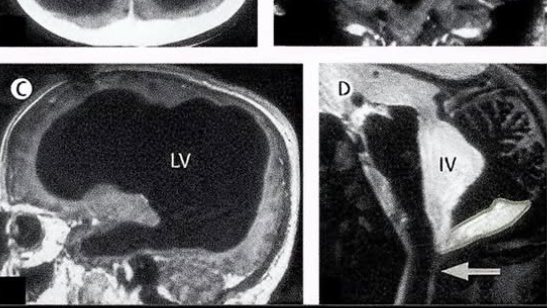

Lekari u Francuskoj su bili šokirani kada su otkrili da pacijentu koji se javio zbog slabosti u nozi nedostaje gotovo 90% moždanog tkiva. Na snimku je otkriveno da mu je lobanja većinski ispunjena tečnošću, te da poseduje samo tanak sloj moždanog tkiva. Dijagnostikovan mu je hidrocefalus.

Ono što ovaj slučaj čini još neobičnijim jeste to što je čovek vodio potpuno normalan život - imao je porodicu, posao i IQ 84, dakle tek nešto niži od proseka. Bio je potpuno svestan i normalno je funkcionisao.

Ovaj neobičan slučaj je naterao naučnike da se još jednom zapitaju - šta zaista formira našu svest?